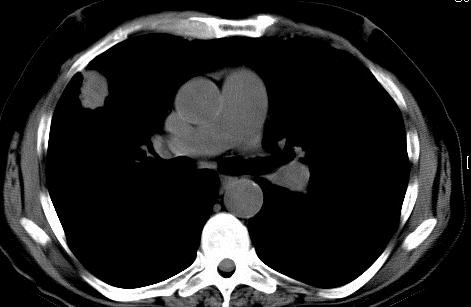

二、影像学随访 增强CT: 一次/3/6/9/12/18/24月;PDG-PET/CT 6/12/18/24月。 病例1